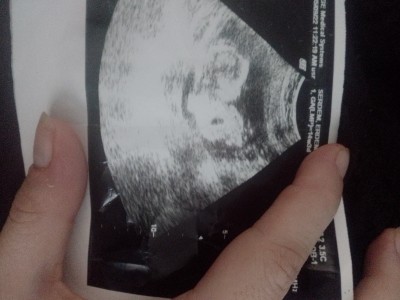

Erkek geçti gönlümden

Evet erkek bende gördüm,;))